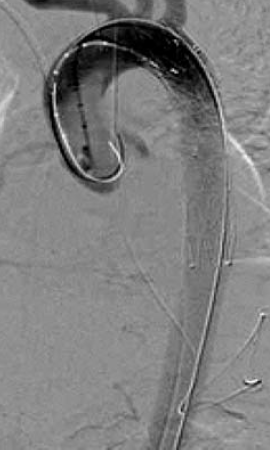

5. ábra.

A 4. ábrán mutatott eset megoldása stent graft beültetéssel.

4. 22 éves fiatal ffi motorbaleset során szenvedett el mellkasi zúzódást, ami a típusos szakaszon álaneurysma képződéssel társult. A diagnózist mellkas röntgenfelvételek és DSA biztosította. Felkartörés rögzítést követően stabil morfológiai állapotban, 20 nappal a sérülés után stentgraft beültetést végeztünk subclavia transpositio nélkül (4.,5. ábra).